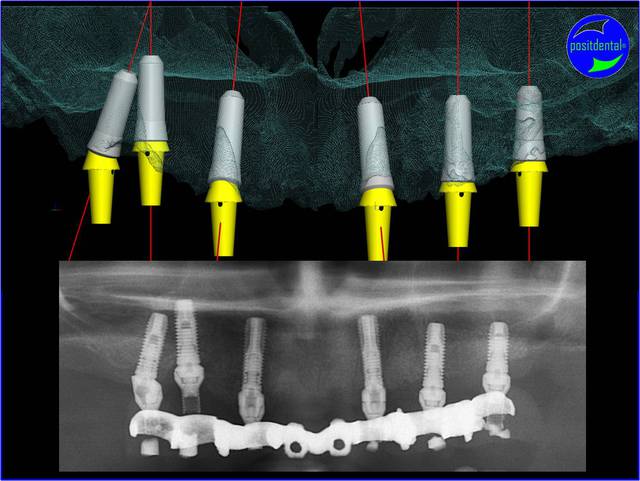

De la Simulation Implantaire Assistée par Ordinateur à la réalité du "terrain".

A) photo clinique

B) image de la modélisation 3D post opératoire issue de la S.I.A.O.

on peut observer que la planification est réalisée en rapport de l'implant Zimmer sur 24 ostéointégré et que les selles du guide juxta osseux sont réduites pour une chirurgie à minima.